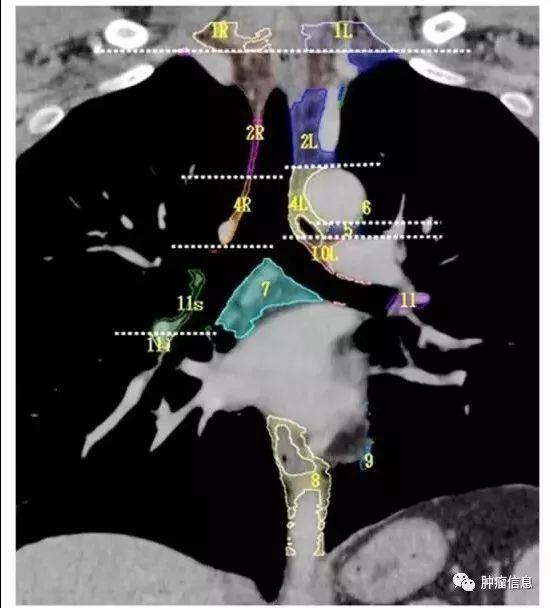

胸部淋巴结分区范围及勾画

1、最高纵隔淋巴结。2、上气管旁淋巴结。3、血管前和气管后淋巴结。4、下气管旁淋巴结。5、主动脉下淋巴结。6、主动脉旁淋巴结。7、隆突下淋巴结。8、食管旁淋巴结。9、肺韧带淋巴结。10、肺门淋巴结。11、叶间淋巴结。12、叶支气管淋巴结。13、段支气管旁淋巴结。14、亚段支气管旁淋巴结。

第1组淋巴结

下颈、锁骨上、胸骨切迹淋巴结上界:环状软骨下缘下界:锁骨、胸骨柄上缘气管中线为1L和1R的分界线。

第2组淋巴结

2R:右侧上气管旁,自胸骨柄上界至无名静脉足侧与气管交汇处,自气管右侧至气管左侧缘。2L:左侧上气管旁,自胸骨柄上缘至主动脉弓上缘,气管左侧缘以左。气管左侧缘是2R和2L的分界线。

第3组淋巴结

第3组淋巴结分为3a和3p:3a:前部的血管前淋巴结上界:胸膜顶下界:隆突水平前界:胸骨后后界:上腔静脉前缘3p:后部的气管后淋巴结上界:胸膜顶下界:隆突水平

第4组淋巴结

4R:右侧下气管旁,自无名静脉与气管交界区至奇静脉,自气管右侧至气管左侧缘。上界:无名静脉与气管交叉处下缘下界:奇静脉下缘4L:左侧下气管旁,自主动脉弓上缘至左侧主肺动脉上缘,气管左侧缘以左。上界:主动脉弓上缘下界:左肺动脉干上缘气管左侧的矢状面是4L与4R分界线。

第5组淋巴结

主动脉下淋巴结:位于主肺动脉窗肺动脉韧带外侧。上界:主动脉弓下缘下界:左肺动脉干下缘

第6组淋巴结

主动脉旁淋巴结:位于升主动脉,主动脉弓的前面和两侧,迷走神经前面。上界:主动脉弓上缘切线下界:主动脉弓下缘

第7组淋巴结区

隆突下淋巴结:隆突下3cm内,与肺内下叶支气管、动脉无关。上界:气管隆突下界:左侧为下叶支气管上缘、右侧为中间支气管下缘

第8组淋巴结

食管旁淋巴结:自隆突下沿食管延伸至膈肌食管裂孔。上界:左侧为下叶支气管上缘、右侧为中间支气管下缘下界:膈肌

第9组淋巴结

肺韧带淋巴结:紧贴下肺静脉之下缘,下肺韧带之内的淋巴结。上界:下肺静脉下界:膈肌

第10组淋巴结

与主支气管和肺门血管相邻的淋巴结上界:右侧奇静脉下缘,在左侧是肺动静脉的上缘。下界:双侧叶间区域

第11组淋巴结

第11组即肺叶间淋巴结,位于支气管分叉处。左侧第11组淋巴结位于第二隆突的下方。右侧的第11组淋巴结又区分为11s(右侧上叶支气管和中间支气管之间)和11i(右侧中叶支气管和下叶支气管之间)。